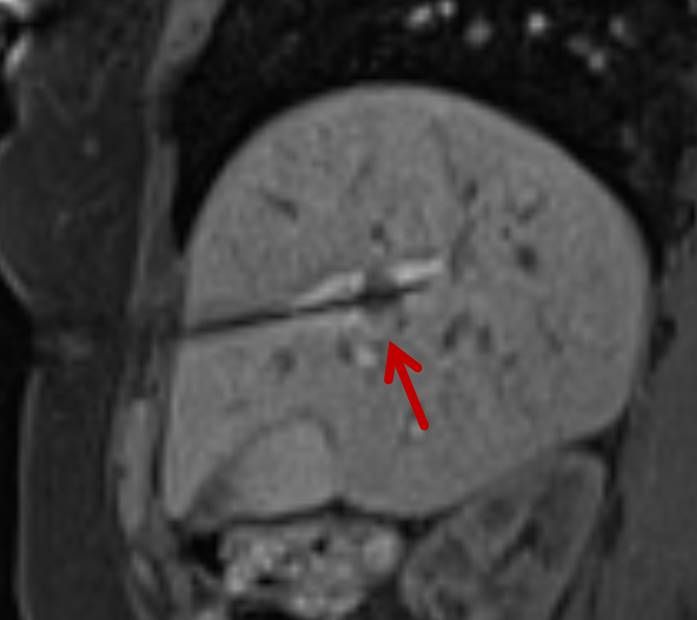

Abbildung: Bei diesem Patienten wurde ein im Röntgen nur schlecht sichtbarer Knochentumor vor der Operation unter MRT-Kontrolle mit kleinen röntgendichten Spiralen („Coils“) markiert. Damit hat der Operateur eine optimale Darstellung des Tumorbereichs bzw. der Tumorgrenzen und kann gezielter, schonender und effektiver operieren.